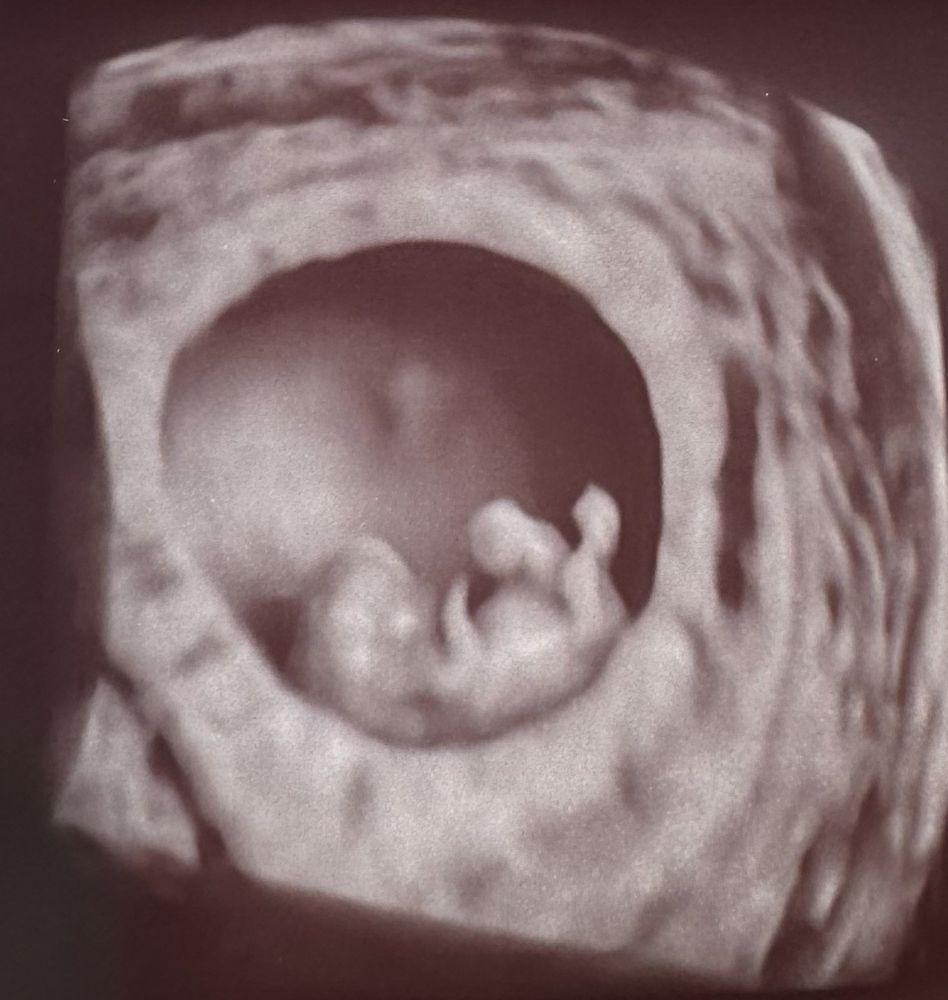

Замечательное фото! 😍 А подскажите, пожалуйста, фамилию узиста (на будущее так сказать))

Guanciotte, ☺️ Ляпунов Александр. Женщины обычно делают будто линейкой под диваном пробку от вина достать пытаются, а тут прям очень аккуратно. Мне гинеколог посоветовала и еще в списке были Костюков и Хегай, но к ним записи не было так что ничего не могу сказать 😁

Дарующая жизнь , да. У него там. Ну я почитала что на таком раннем сроке желудок еще не сформировался и так как места у эмбриона мало все вываливается наружу и формируется в мешочке а потом к 12 неделе всасывается в живот. Так что точно скажут только на первом скрининге. Свет я впервые видела. Оранжевым все на экране светилось и врач игрался больше меньше света включал и вертел чтоб картинка была получше. Там все все видно становилось 3д все как есть 😁

Ой как прикольно.)) Такой пупсик.) Мне кстати тоже сказали, что плод крупный, но такое бывает и это нормально. У меня на тот моменты было 7 недель, а по размерам был на 8. У нас почти одинаковый срок.) У меня на этой 10 недель.😅 Время летит.) Не переживайте.) Все будет хорошо.)❤️ Сама жду уже скрининга.)

Классная фотка😀☺️

Лили, вот техника то дошла😀видно дом и тот кто в нем😁

"Фотка" огонь! Интересно, что пространства там прилично внутри, целый дом🙂

Елена, даа) там прилично места для танцев и под определенным углом датчика внутри него видно еще один внутренний круг из тонкой материи. Это мне сказали уже околоплодный пузырь или как там, оболочка в которой он плавает. До чего техника дошла 🤣